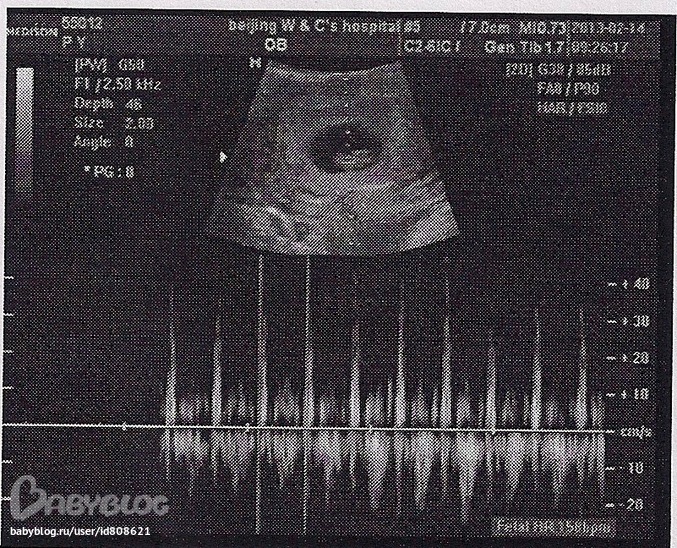

Наша бусинка уже не бусинка :) превратилась в толстого червячка. Лежит и спит себе тихонько, не шевелится. Вот только бешено пульсирует маленькое сердечко. 158 ударов в минуту.